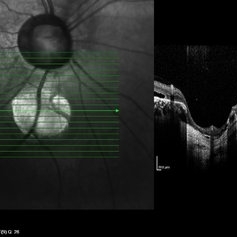

Coloboma of Disc & Choroid

Coloboma of Disc & Choroid

Oct 6 2012 by Hamid Ahmadieh, MD

OCT image of a 25-year-old woman with serous retinal detachment secondary to coloboma of disc associated with coloboma of choroid.

Photographer: Hamid Ahmadieh, MD, Ophthalmic Research Center, Labbafinejad Medical Center, Shahid Beheshti University of Medical Sciences

Imaging device: Heidelberg Spectralis

Condition/keywords: coloboma of choroid, coloboma of optic disc, optical coherence tomography (OCT), serous retinal detachment